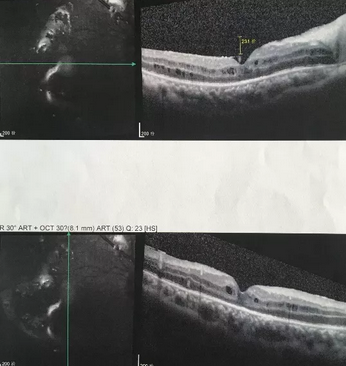

独眼,视网膜全脱离已成窄漏斗状、陈旧性葡萄膜炎、瞳孔后黏连无法散大,且并发白内障使得视网膜周边部细节情况无法看清,左眼已无光感,角膜白斑,瞳孔闭锁,还填充着硅油。右眼既往葡萄膜炎病因不清,一年中发病3、4 次都是用激素医治。左眼多年前是“天那水”溅入后又发生玻璃体出血手术后……令人担心的是这次我们克服重重困难救治全部脱离的视网膜 后,可能会面对长期慢性葡萄膜炎、长期药物医治的继发性高眼压,以及葡萄膜炎的再次复发等,稍有不慎就是不逆性致盲了。

“接班时怯医生已有交代关注这个术后病人的眼压,昨晚8点测量为22mmHg,已给予停用降眼压药物。昨晚打开眼罩测量眼压时病人说能看到地上的凳子了,凳子腿是不锈钢的!!非常的激动,护士赶快重新换药给予术眼包好。”当夜班值班的赵伟红医生说完这句话,赵院长悬着的一颗心才终于放下,便有了开头那感人的一幕。